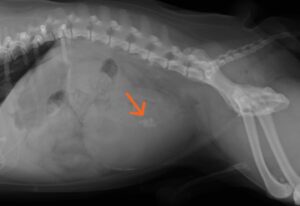

レントゲン上の結石